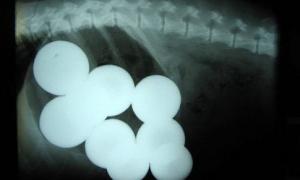

Пес, який проковтнув 9 більярдних куль, переміг у конкурсі рентгенівських знімків

Ветеринари Сполучених Штатів узяли участь у конкурсі на найнеймовірніший рентгенівський знімок, аби показати, які несподівані речі іноді ковтають домашні улюбленці.